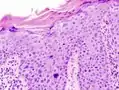

Maladie de Bowen

La maladie de Bowen est un carcinome épidermoïde (ou spinocellulaire) intra-épidermique (carcinome in situ), favorisé par le soleil et l'arsenic. Elle peut toucher la peau mais aussi les muqueuses[1]. Elle se présente sous la forme d'une lésion brun rougeâtre arrondie ou arciforme bien limitée dont la surface est un peu surélevée et squameuse[1]. Son diagnostic est histologique. Son évolution est très lente et la maladie présente un excellent pronostic de guérison. En revanche, en l'absence d'un diagnostic et d'un traitement approprié, elle évolue lentement mais sûrement vers un véritable carcinome épidermoïde invasif[1].